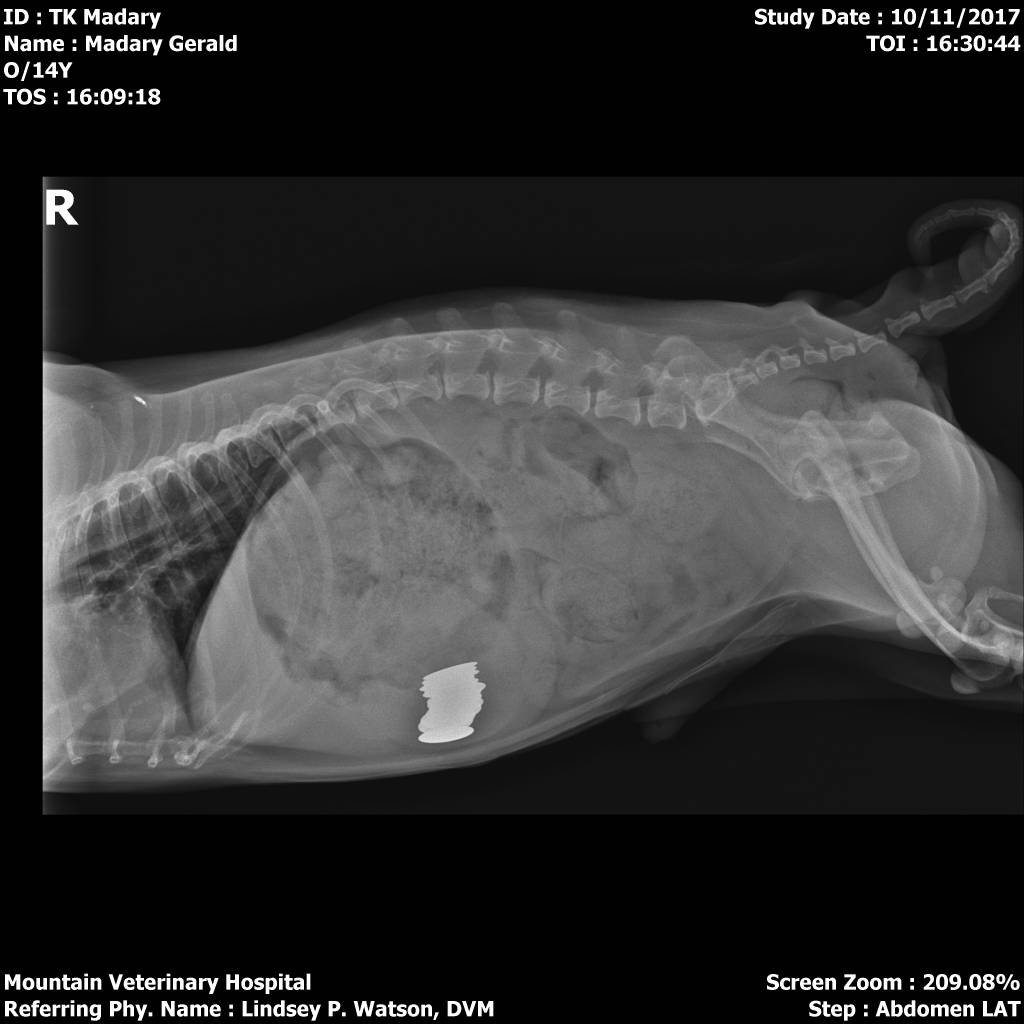

They Ate What?! X-ray Contest 2018They ate this: Check out the winner, runners-up, and honorable mentions October 1, 2018 < Previous Entry Next Entry > Pages: 1 2 3 4 5 6 7 8 9 10 11 12 13 14